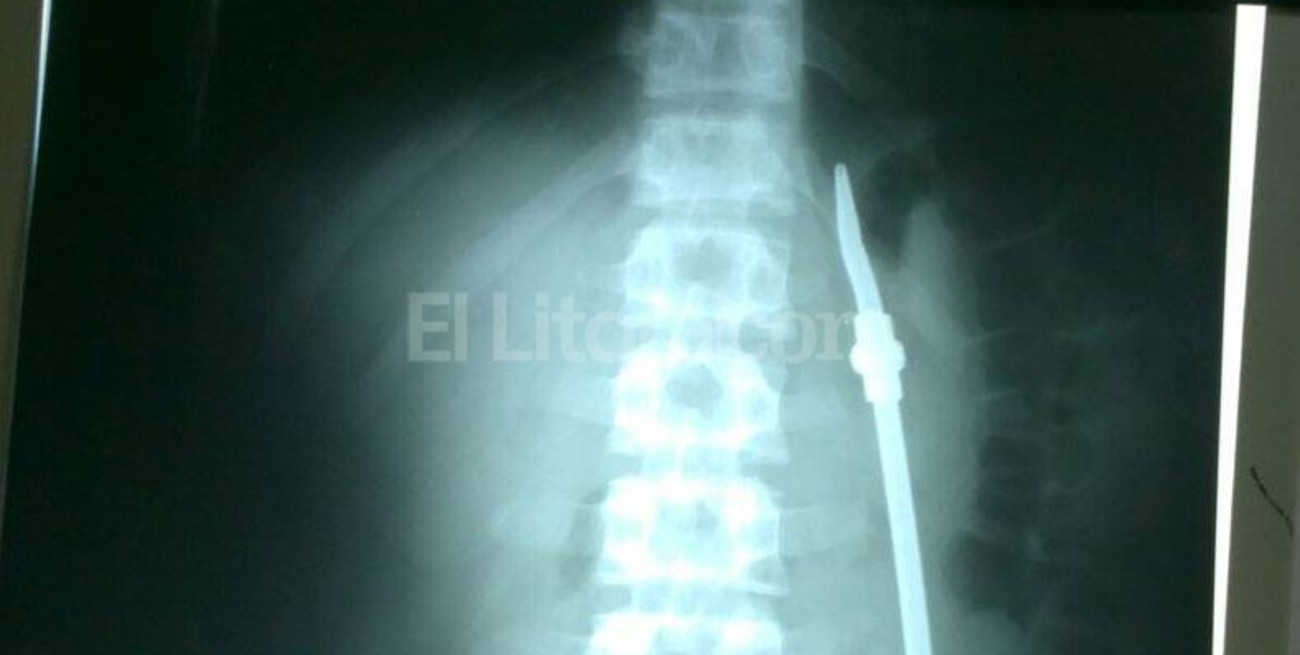

Un preso, que está alojado en la Unidad Penal n° 1 de Paraná, partió en dos una bombilla y se la tragó mientras tomaba mate junto a otros reclusos.

Según publica El Once, tras conocerse el episodio el sujeto fue derivado al hospital San Martín donde fue intervenido quirúrgicamente.